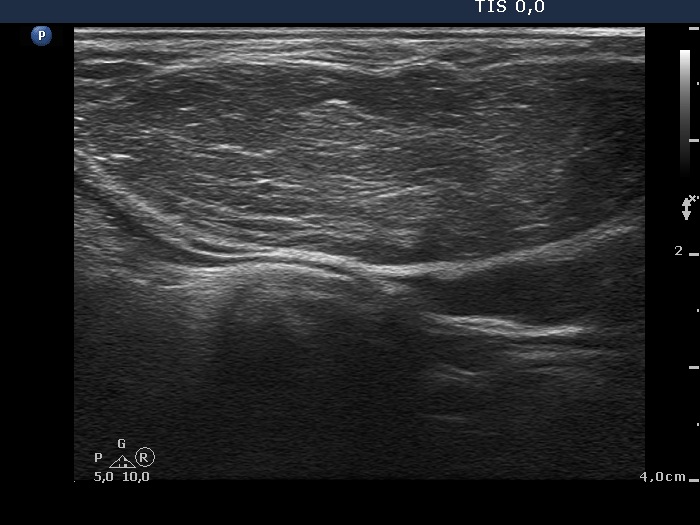

Ultrasonography: the thyroids were echonormal and contained no discrete lesion. According to the palpable mass a large, moderately hypoechogenic lesion was found with pronounced fibrosis. The lesion presented a type 1 vascular pattern.

Diagnosis: lipoma in the neck.